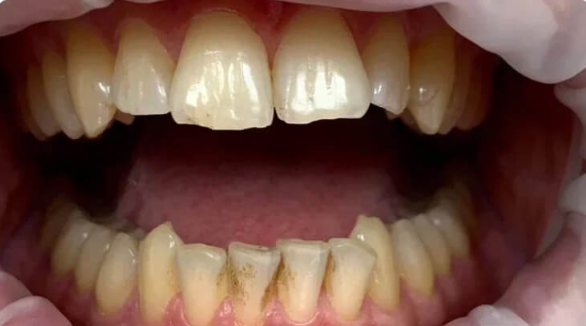

На странице представлено портфолио стоматологий Санкт-Петербурга с работами до и после профессиональной чистки зубов. В нашем портфолио собраны разные клинические случаи: от удаления незначительного налета до снятия массивного поддесневого камня. Здесь вы можете увидеть, как возвращается естественный цвет и внешний вид зубов после процедуры. Изучите результаты до и после чистки зубов, чтобы увидеть реальный эффект и выбрать клинику в Санкт-Петербурге, где профессиональная гигиена поможет вернуть зубам здоровый вид.

Профессиональная гигиена полости рта.